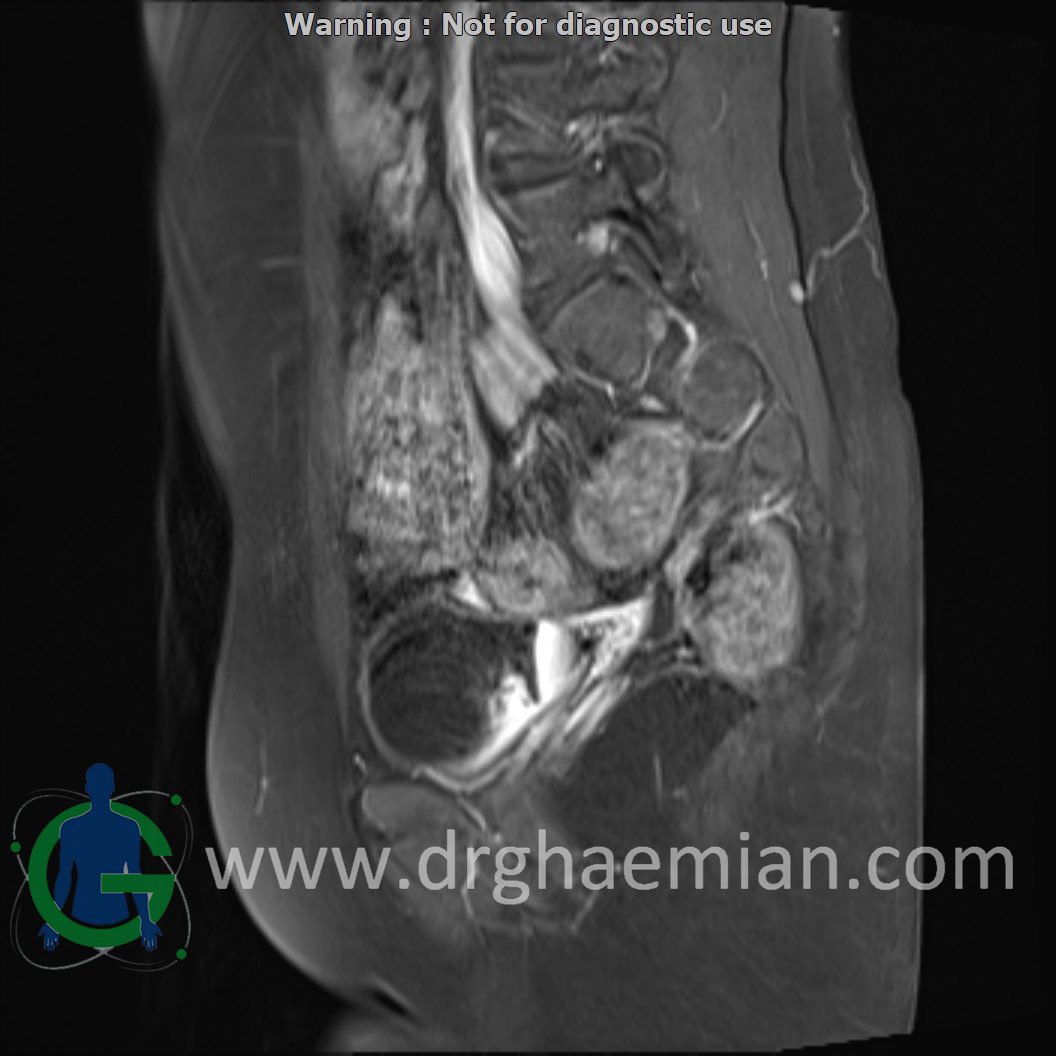

ام آر آی لگن یک روش تصویربرداری است که از طریق دستگاهی با آهنرباهای قوی و امواج رادیویی از ناحیه بین استخوان های ران تصاویری می سازد.در این کیس دیسژنزی غدد جنسی همراه با رحم و واژن هیپوپلاستیک نشان دهننده سندرم سویر ….

ABDOMEN & PELVIC MRI ( with and without contrast )

Technique : precontrast :axial T2 haste , axial vibe – dixon – coronal vibe – dixon – sagittal T2/haste – sagittal blade – coronal T2/FATSAT- axial T2-FATSAT- axial DWI with ADC.

post contrast :coronal vibe dixon – sagittal vibe dixon – axial vibe dixon – coronal & sagittal T1

Complete gonadal dysgenesis with hypoplastic uterus & vagina suggestive of swyer syndrome is seen.

Clinical crrelation is recommended.